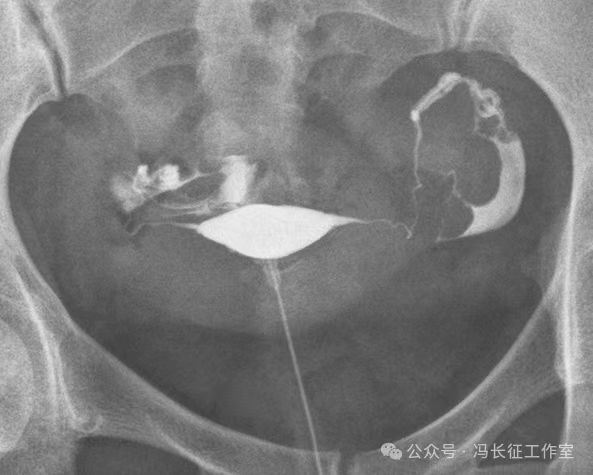

下面是一例正常子宫输卵管造影图(4张片)

微信图片_20240215160243.jpg